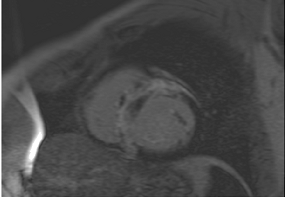

Table 3 summarises a suggested CMR scan protocol for the diagnosis of presumed HHD and differential diagnosis of patients with a “thickened left ventricle”.

Table 3.

The cardiovascular magnetic resonance protocol used for assessment of hypertensive patients. The described protocol can be acquired within 45–50 min. Images are examples from patients with hypertensive heart disease.

To avoid the low but important risks of endomyocardial biopsy, which can have an overall complication rate of up to 6% [2], myocardial fibrosis can be assessed non-invasively using CMR: LGE is suitable for detecting irreversible replacement fibrosis and myocardial scarring and T1/ECV mapping for detection of potentially reversible (reactive) interstitial and more diffuse fibrosis (not detectable by LGE) (Figure 2).

9. Tissue Characterisation with Late Gadolinium Enhancement

LGE has become the reference standard for non-invasive imaging of myocardial scar and focal fibrosis [40]. Gadolinium chelates are interstitial agents that cannot penetrate healthy intact cell membranes. Therefore, they remain in the interstitial space and accumulate in areas of cell injury/necrosis and focal fibrosis where this is expanded, while in healthy regions, contrast more readily washes out [41]. Specific LGE patterns are seen in different diseases (e.g., subendocardial fibrosis in CAD, patchy epicardial/mid-wall fibrosis in areas of hypertrophy in HCM). Minor areas of LGE can be detected in up to 50% of patients with HHD, but there is no specific pattern (in 95% of the non-ischaemic LGE distribution) [42]. If present, LGE is often found in the basal to mid-septal, inferior, and inferolateral segments in patients with HHD [42]. The severity of diastolic dysfunction increases with the extent of fibrosis by LGE [25,31]. Furthermore, focal fibrosis/LGE may be a substrate for ventricular arrhythmia and is associated with sudden cardiac death [31].